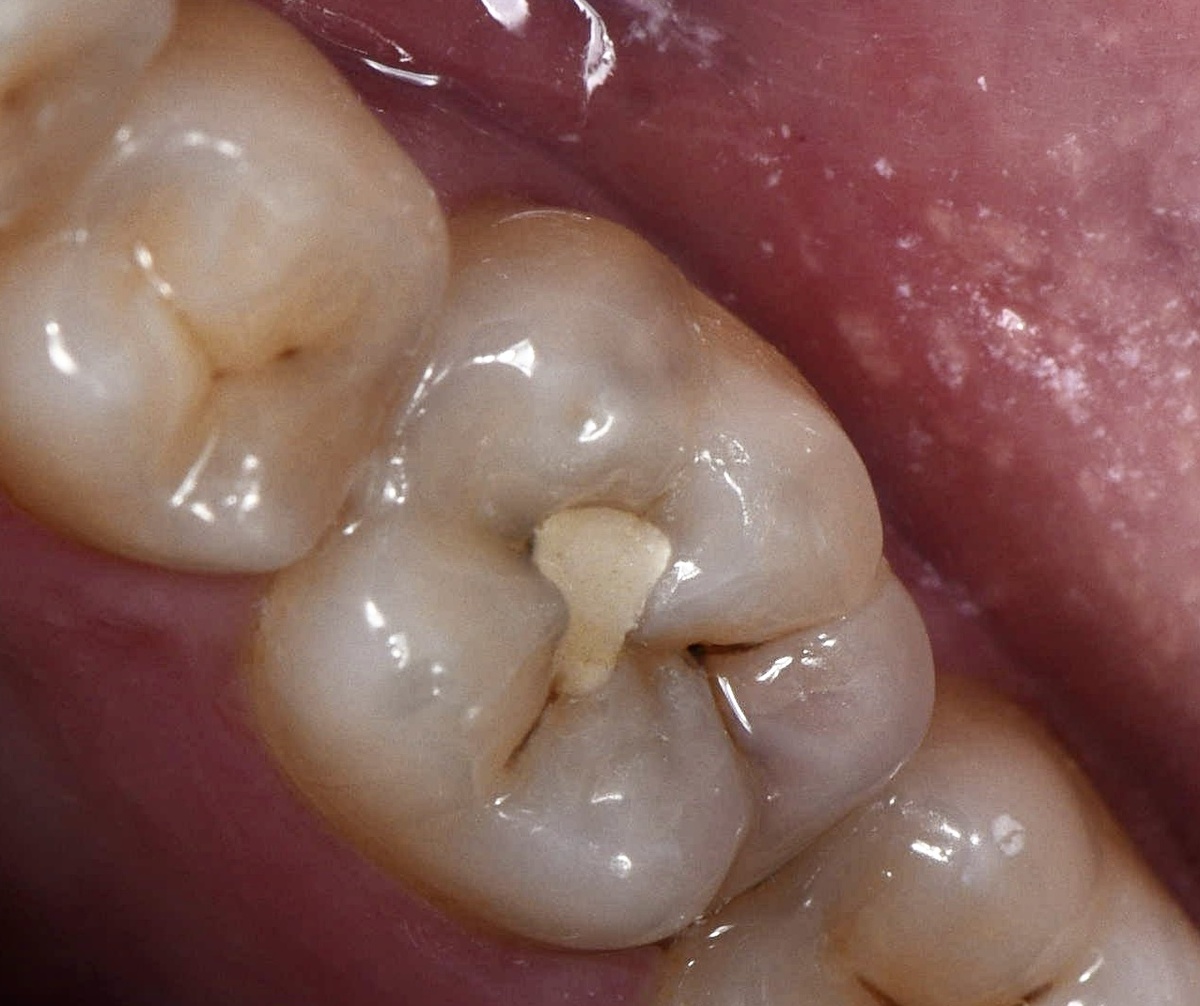

Фиссура — углубление или бороздка на жевательной поверхности зуба. У детей такие впадины часто бывают очень глубокими и узкими. Там легко застревает пища и начинают размножаться бактерии. Щеткой бывает очень трудно вычистить налет.

Чтобы защитить зубы, на них наносят специальный защитный материал, который запечатывает эти углубления. Процедура называется герметизацией фиссур. Герметик делает поверхность зуба более гладкой, ее легче очищать от налета.